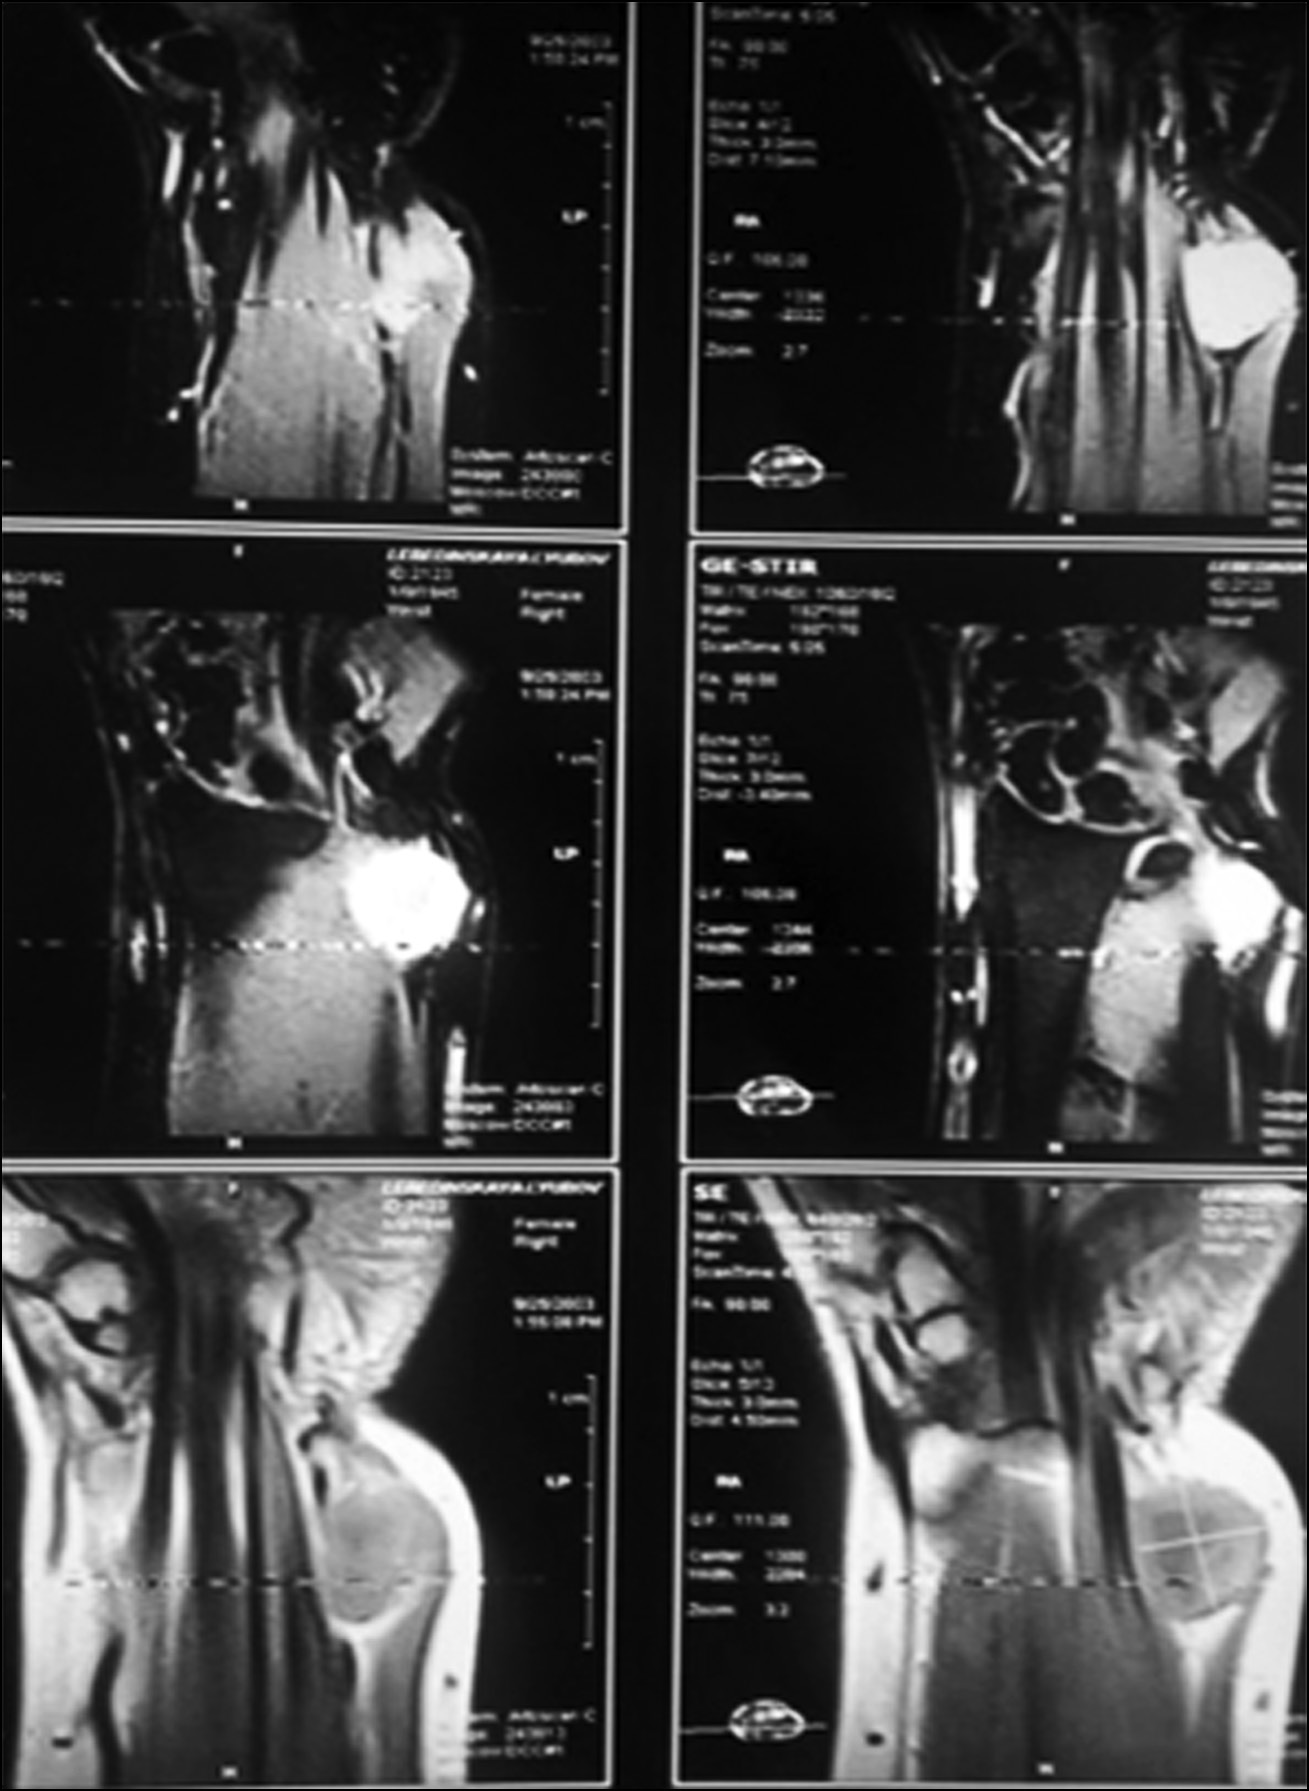

Применение МРТ с высокой разрешающей способностью (на аппаратах мощностью 1,5 Тесла и более) позволяло определять очаги размером менее 0,3 мм, уточнять их расположение и сделать предварительные заключения о природе опухоли, характере васкуляризации (рис. 11).

Рис. 11. МРТ: фиброма лучезапястного сустава.

Fig. 11. MRI: the fibroma of wrist joint.

МРТ была выполнена в 53 случаях. В 3 случаях фибролипоматоза срединного нерва с макродактилией при проведении МРТ были обнаружены характерные МР-признаки: продольно ориентированные цилиндрические нервные пучки, окружённые жировой тканью, входящей в состав пучков.

В одном случае у пациента с предварительным диагнозом «синовиальная киста», предварительно подтверждённым результатами УЗИ и МРТ, выполненной на аппарате мощностью 0,5 Тесла, на операции была обнаружена кавернозная гемангиома. Таким образом, в клинически неоднозначных случаях ДОМТ кисти была подтверждена необходимость проведения МРТ с высокой разрешающей способностью (на аппаратах мощностью 1,5 Тесла и выше).

Была выявлена целесообразность обязательного предварительного МРТ-исследования на аппаратуре высокой мощности, которое в нашей работе проводилось в 53 случаях.